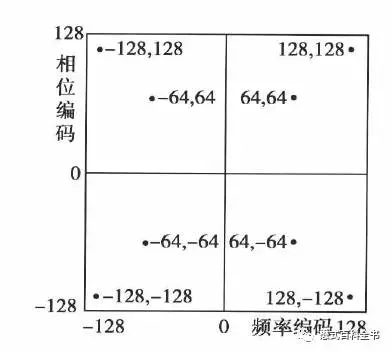

这里什么叫共轭对称呢?共轭对称的意思是:当一个函数,它的实部为偶函数,虚部为奇函数的时候,并且满足f(x)=f(-x),这个函数就叫共轭对称函数。简单的说就是,把K空间分为四个象限的话,每个对角线都是对称的。

图7-8:K空间共轭对称示意图。

相位编码方向也是对称的。因为每次相位编码梯度会变化,在K空间中心的时候,不施加相位编码梯度(相位编码梯度为0),在两边分别依次递增相位编码梯度,但是两边的方向相反,所以在相位编方向,K空间也是对称的。

图10:相位编码方向上K空间的对称性

利用K空间的对称性,我们可以做什么呢?当然是加速扫描了。因为,传统来说,我们要重建磁共振图像,得把K空间数据填满,特别是相位编码方向(因为相位编码步级决定扫描时间);如果我们只填充一半相位编码线,这样的话,扫描时间就节约了,在利用K空间的共轭对称性,利用数学算法,算出K空间的另外一半,这样也可以重建图像。

图11:利用K空间对称性,做快速扫描

理论上,在相位编码方向(Ky),由于K空间相位编码方向的对称性,我们只需要填充一半的相位编码线,就可以利用数学算出另外一半,然后重建图像节约扫描时间。这种只填充K空间一半(一半以上)的相位编码线的方法叫做半扫描(部分K空间技术)。